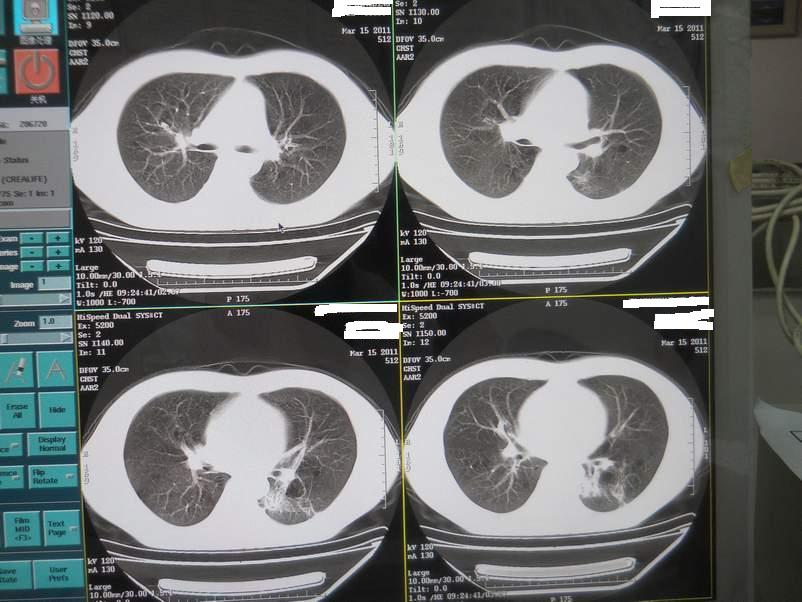

肺霉菌感染

男,22岁,一年前诊断马尔菲尼青霉菌感染,多次复查CT。多次HIV阴性。最近两次CT图片。有实验室结果。

最近实验室检查结果:霉菌感染。